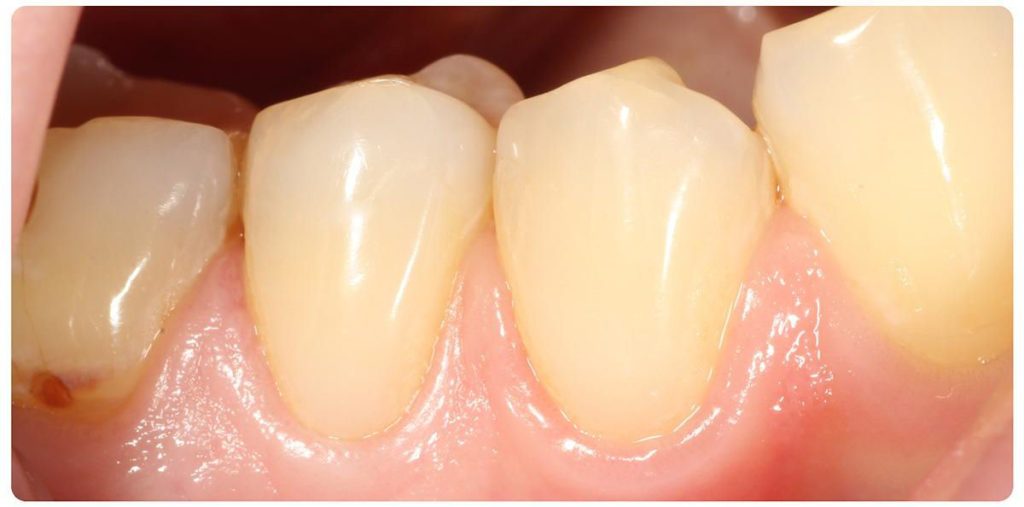

Podczas gdy w dolnym łuku dr Michał Mokijewski przeprowadzał zabiegi regeneracyjne i implantacje, zajęłyśmy się leczeniem łuku górnego.

Zgodnie z zasadą, że prace protetyczne powinny być oparte na zdrowych i solidnych fundamentach, zaczęłyśmy od podstaw – wymiana nieszczelnych wypełnień, powtórne leczenia kanałowe.

Praca została zwieńczona odbudową zębów koronami cyrkonowymi. Brakujący ząb, którego nie można było uzupełnić implantem z powodu za małej ilości miejsca, odtworzono za pomocą cyrkonowego mostu.

Zgodnie z życzeniem Pacjentki poprawiony został kolor i kształt zębów. Kamuflaż protetyczny umożliwił także skorygowanie asymetrii.

Dzięki profesjonalizmowi naszych lekarzy, Pacjentka ma teraz zdrowy, piękny uśmiech!

Wykonano odbudowę koronami cyrkonowymi, dla harmonii włączono w pracę również prawą dwójkę.

Zachwycona efektem końcowym Pacjentka z radością eksponuje nowy uśmiech i, jak sama przyznaje, „czuje się znów tak, jak za młodu„. Co też potwierdza Jej mąż